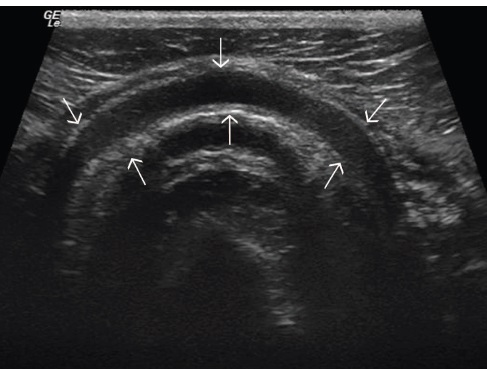

Fig 5: Transverse plane ultrasound of the ventral aspect of

the cricoid cartilage (arrows) of a normal larynx. Left is to

the right of the image and right is to the left